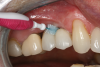

Professional maintenance devices: scalers (manual, sonic, ultrasonic) and polishers.Clinicians performing deplaquing or calculus removal from an implant-supported restoration need to be aware they may possibly engage different types of surfaces, eg, restoration, smooth abutment, rough implant surface. To preclude roughening an abutment surface, a plastic instrument could be employed manually, even though residues from the instrument may be left behind.77 Metal sonic and ultrasonic instruments can be used when scaling abutments; however, to avoid micro-roughening of abutments with these instruments, nylon sleeves and plastic inserts can be utilized (Figure 3).78,79 Because plastic instruments are not effective in debriding rough-surface implants, metal hand or ultrasonic instrumentation can be used to clean an implant body that is inherently rough (Figure 4).82,83 The surfaces of titanium implants can be polished using a rubber cup with a non-abrasive paste.65 Finally, the patient's informed consent form should include the responsibility to be compliant with personal and professional peri-implant maintenance.

Fig 3. Ultrasonic insert with

nylon tip can be used for debriding implant abutment surface.

Figure 3